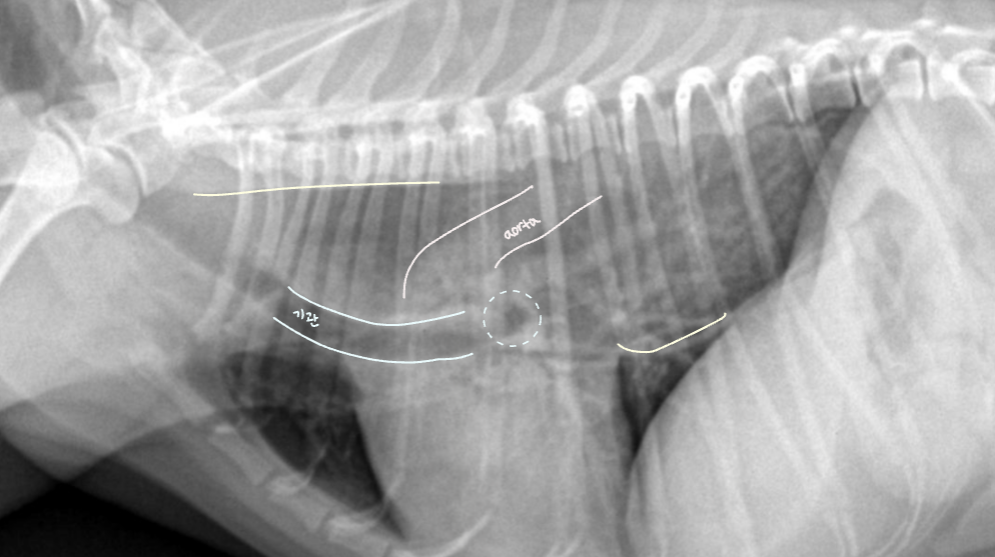

Anatomy (๋ณต๊ฐ ์ฅ๊ธฐ์ ์์น)

| Lateral |

|---|

| - stomach : ๊ฐ ์๋ gas๊ฐ ์ฐจ ์๋ ๊ตฌ์กฐ (์ฐจ ์๋ ๊ฑด ๋ค๋ฅผ ์ ์์) - duodenum : ์์ ๊ฐ์ด๋ฐ์์ ๋ป์ด๋๊ฐ - cecum : ์ฐ์ธก, ์ฌ์ฅ ์ฃผ๋ณ, gas๊ฐ ์ฐจ ์๋ ์ํ์ฑ ๊ตฌ์กฐ. (์์ ๋ฑ์ผ๋ก ์์น ๋ณํ ์ ์์) |